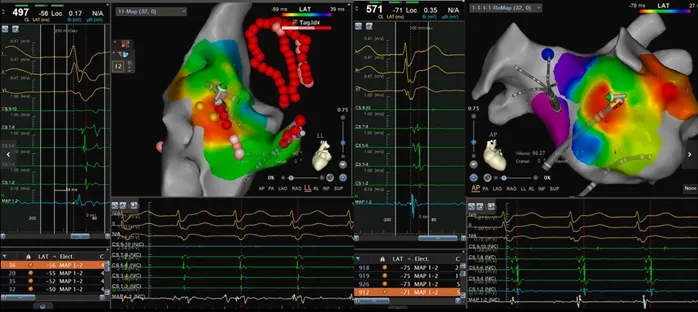

1)房速1:心动过速周长450ms,呈向心性冠状窦激动顺序。右房标测显示最早激动点位于希氏束附近;经房间隔穿刺后行左房标测确定最早激动点位于二尖瓣峡部上方(约11点钟方向)(图7)。

2)房速2:亦呈向心性冠状窦激动顺序,但发作持续时间较短。初步标测提示右房激动早于左房(左房最早激动点疑似在Bachmann束插入处附近)(图8)。随后精细标测右房,将最早激动点定位于界嵴下部(图9)。

图7 房速1的标测(最早激动点位于二尖瓣环高位)

图8 房速2的标测(右房优先激动)

图注:左房最早激动点疑似位于Bachmann束插入处附近

图9 房速2的标测

图注:右房最早激动点位于界嵴下部

针对房早起源灶(冠状窦远端/心内膜),采用射频消融(功率35W、温度43°C、灌注速率17 mL/min)放电10秒后房早消失,随后行120秒巩固消融。针对房速1靶点为二尖瓣环上方(11点钟方向)最早激动点,消融(参数同上,巩固消融120秒)成功终止;房速2靶点为界嵴下部最早激动点,消融(参数同上,巩固消融120秒)成功终止。